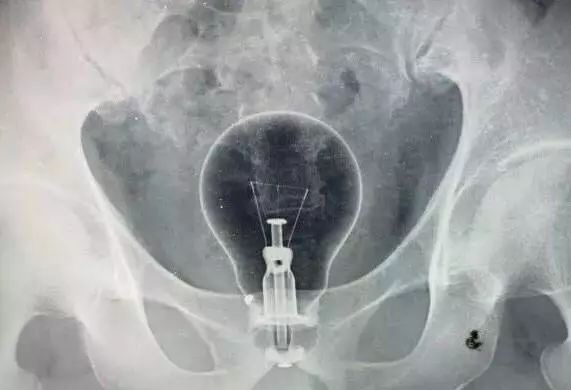

最近急诊科住了一名患者,因为直肠内异物被收治入院。直肠异物并不算什么罕见的事情,只不过这次的异物有点特殊:是个灯泡。

患者是个四十多岁的男性,由于各种原因,不慎将灯泡塞入体内无法取出。后因担心灯泡在体内破裂,故来就医。

三,充分扩肛后,用一根较细的尿管,插入肛门,达到异物近端,接着用注射器往里面注射一些石蜡油,起到润滑的作用。

四,用卵圆钳夹住异物,慢慢往外拉,边拉边转。如果拉的时候,阻力过大,可以往尿管里注射空气,消除负压。